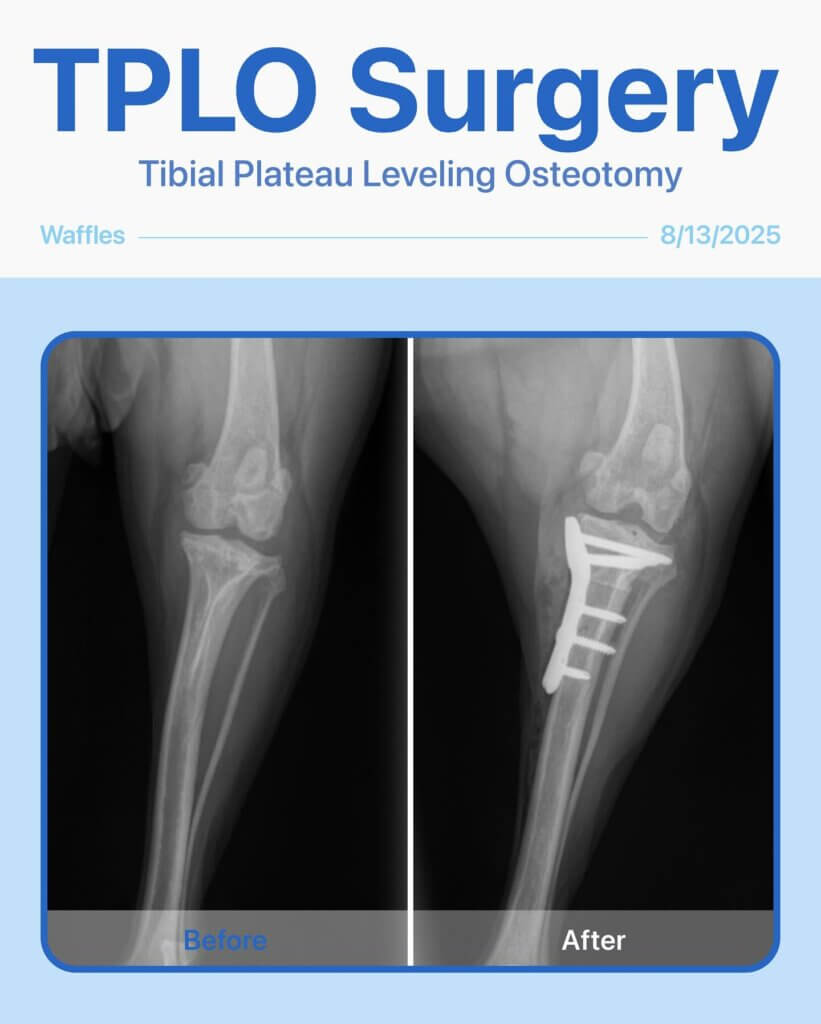

Before & After – TPLO Surgery for Waffle!

Waffle, our sweet 4-year-old girl, came in with a limp in her back left leg and low energy that had been bothering her for a few months. After a thorough physical exam and radiographs, we diagnosed her with a cranial cruciate ligament (CCL) rupture—a common injury in dogs that causes pain, instability, and difficulty walking.

To restore her mobility and relieve pain, Waffle underwent TPLO (Tibial Plateau Leveling Osteotomy) surgery. The procedure went smoothly, and Waffle is on her way to a full recovery!